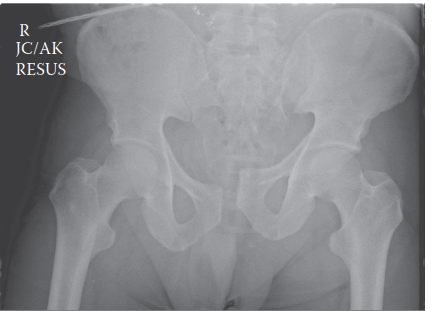

الأشعة السينية الأولية (Initial Trauma Radiographs):

- صورة الحوض الأمامية الخلفية (AP Pelvis): تظهر هذه الصورة أي تباعد في الارتفاق العاني (مفصل العانة الأمامي) أو توسع في المفاصل العجزية الحرقفية، وكسور العجز أو الحرقفة. في حالة المريض محل دراستنا، أظهرت تباعداً كبيراً في الارتفاق العاني (>2.5 سم)، وتوسعاً في المفصل العجزي الحرقفي الأيمن، وكسراً مفتتاً في العجز الأيمن يمتد إلى القناة العصبية (Denis Zone II)، مما يؤكد إصابة حلقة الحوض غير المستقرة.

- صورة المدخل (Inlet View): تُظهر أي إزاحة خلفية أو دوران داخلي لأحد نصفي الحوض.

- صورة المخرج (Outlet View): تكشف عن أي إزاحة عمودية (للأعلى أو للأسفل) لأحد نصفي الحوض، مما يؤكد وجود مكون القص العمودي.

شكل 1: صورة شعاعية أمامية خلفية للحوض تظهر تباعداً كبيراً في الارتفاق العاني، وتوسعاً في المفصل العجزي الحرقفي الأيمن، وتفتتاً في الجناح العجزي الأيمن، مما يدل على إصابة غير مستقرة في حلقة الحوض. -